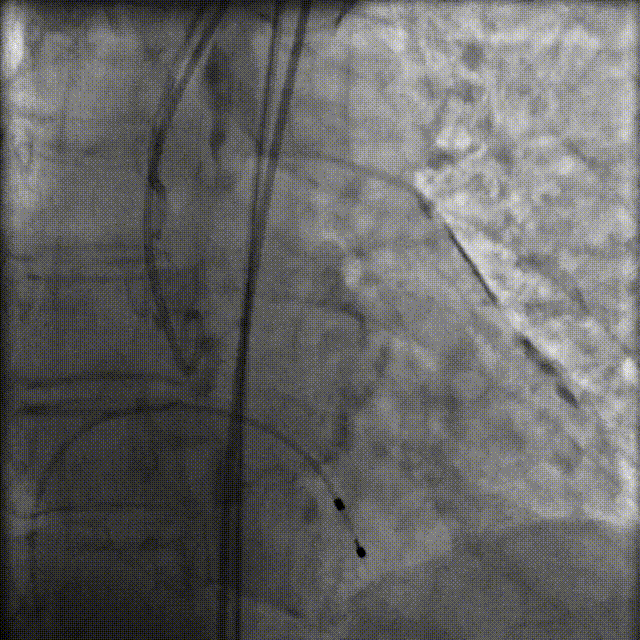

瓣膜释放后主动脉根部造影提示瓣膜膨胀、位置良好,无主动脉瓣反流,未影响冠脉开口

图片

释放后造影